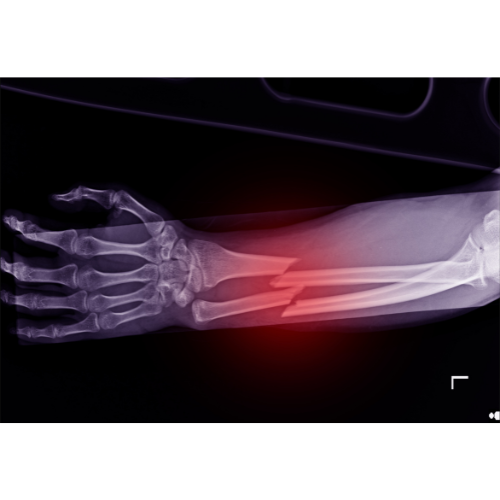

Wrist Fractures

Wrist fractures are breaks in one or more bones around the wrist joint, commonly caused by falls onto an outstretched hand or direct trauma. They can lead to pain, swelling, deformity, and difficulty using the hand.

Distal Radius Fracture

A distal radius fracture is a common type of wrist fracture involving the larger forearm bone near the wrist. It often happens when someone tries to break a fall with their hand.

Who Needs It?

• Severe wrist pain after a fall

• Swelling and bruising around the wrist

• Wrist appearing bent or deformed

• Difficulty moving the wrist or fingers

Benefits:

• Proper alignment of the wrist joint

• Prevents long-term loss of motion

• Reduces risk of arthritis and stiffness

• Promotes strong and stable healing

• Helps restore normal hand function

Forearm Fractures

Forearm fractures involve a break in one or both of the forearm bones – the radius and ulna. These injuries commonly occur due to falls, sports injuries or accidents and can affect the ability to rotate the arm and use the hand.

• Severe pain, swelling or deformity in the forearm after injury

• Difficulty turning the palm up or down

• Inability to lift or grip objects

• Visible bending or abnormal movement of the arm

• Restores proper alignment of the bones

• Preserves normal arm rotation and function

• Reduces pain and swelling

• Prevents long-term stiffness or deformity

• Enables safe and effective healing with return to daily activities